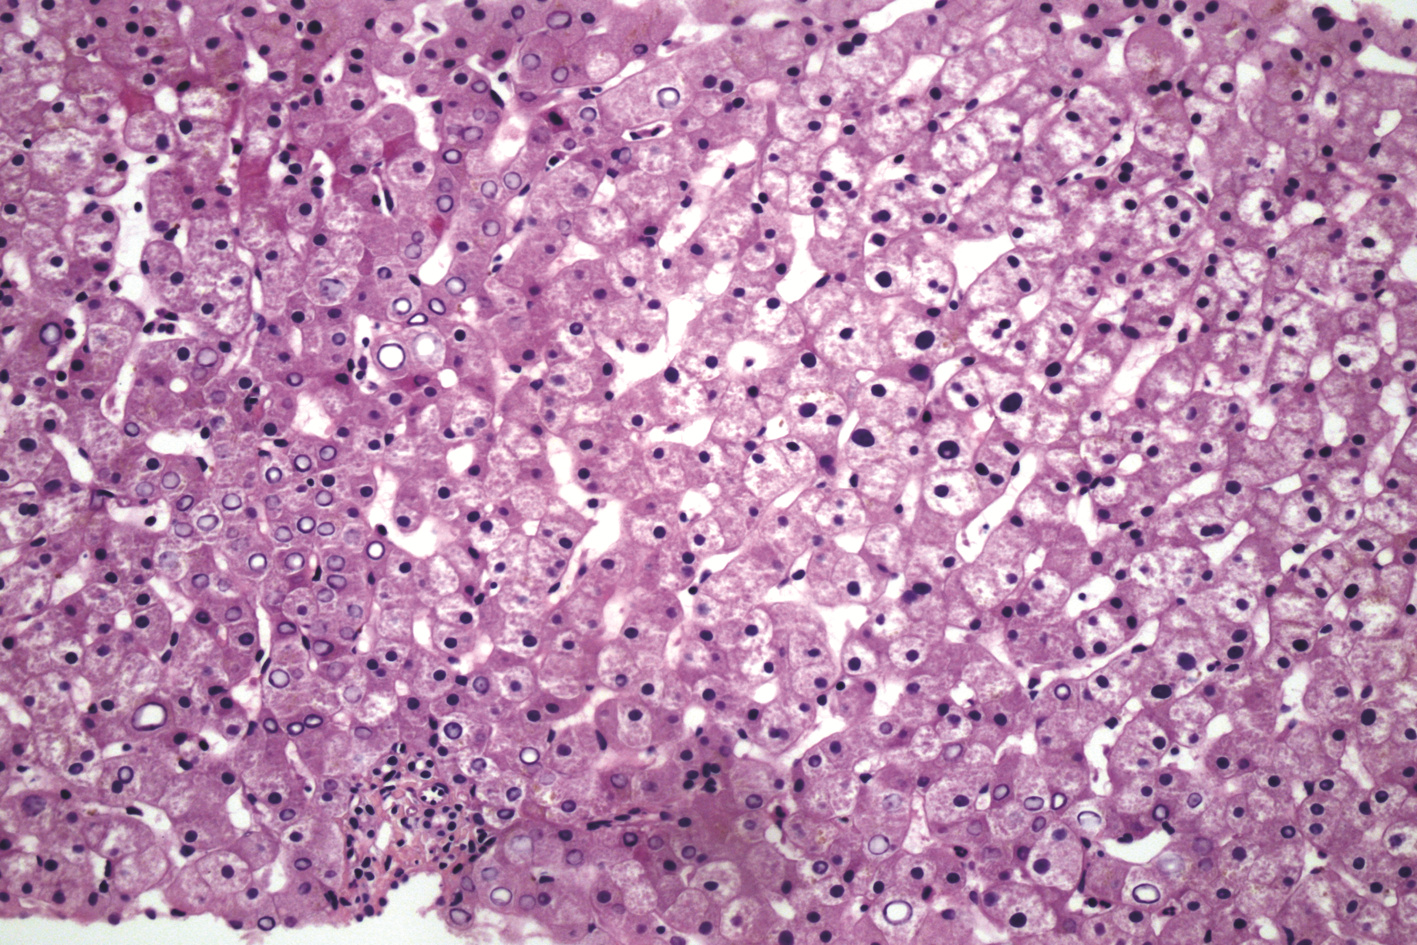

局部栓塞联合靶向免疫综合治疗肝肉瘤样癌1例报告

雷进, 张林枝, 陆荫英, 陈博文, 左石

2022, 38(4): 880-882. DOI: 10.3969/j.issn.1001-5256.2022.04.026

摘要(1323) HTML (453) PDF (3487KB)(82)

摘要: